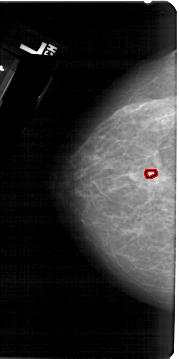

A_1268_1.LEFT_MLO

LEFT_MLO LINES 5491 PIXELS_PER_LINE 2986 BITS_PER_PIXEL 12 RESOLUTION 43.5 OVERLAY

FILE: A_1268_1.LEFT_MLO.OVERLAY

TOTAL_ABNORMALITIES 1

ABNORMALITY 1

LESION_TYPE CALCIFICATION TYPE PLEOMORPHIC DISTRIBUTION CLUSTERED

ASSESSMENT 4

SUBTLETY 4

PATHOLOGY BENIGN

TOTAL_OUTLINES 1

BOUNDARY